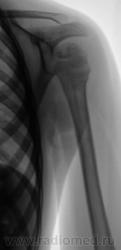

Но у первого пострадавшего помимо перелома и вывиха в плечевом ещё и надрыв/разрыв ключично-акромиального сочленения.

На мой взгляд, вывих спорный.

В обоих случаях перелом хирургической шейки плечевой кости. А почему только в одной проекции? Мы всегда снимаем в двух - в прямой и аксиальной.